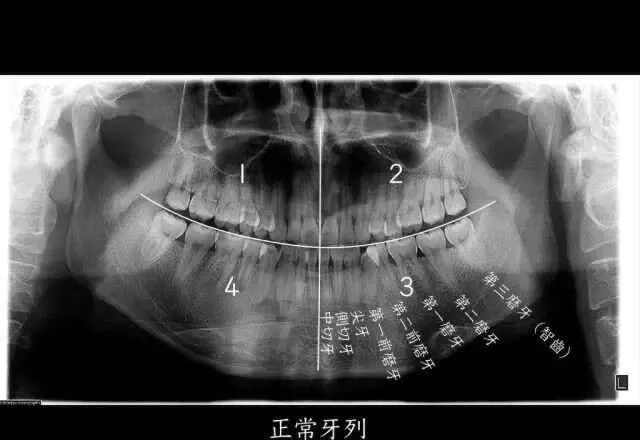

智齿,也就是第三磨牙,位于口腔最远最深的位置。图源:作者

如果我们把一个正常成年人的口腔分为左上、左下、右上、右下四个区域的话,每个区域会有 8 个牙齿,长在最后的第8颗牙齿,就是我们口中的“智齿”,也是我们的第三磨牙。